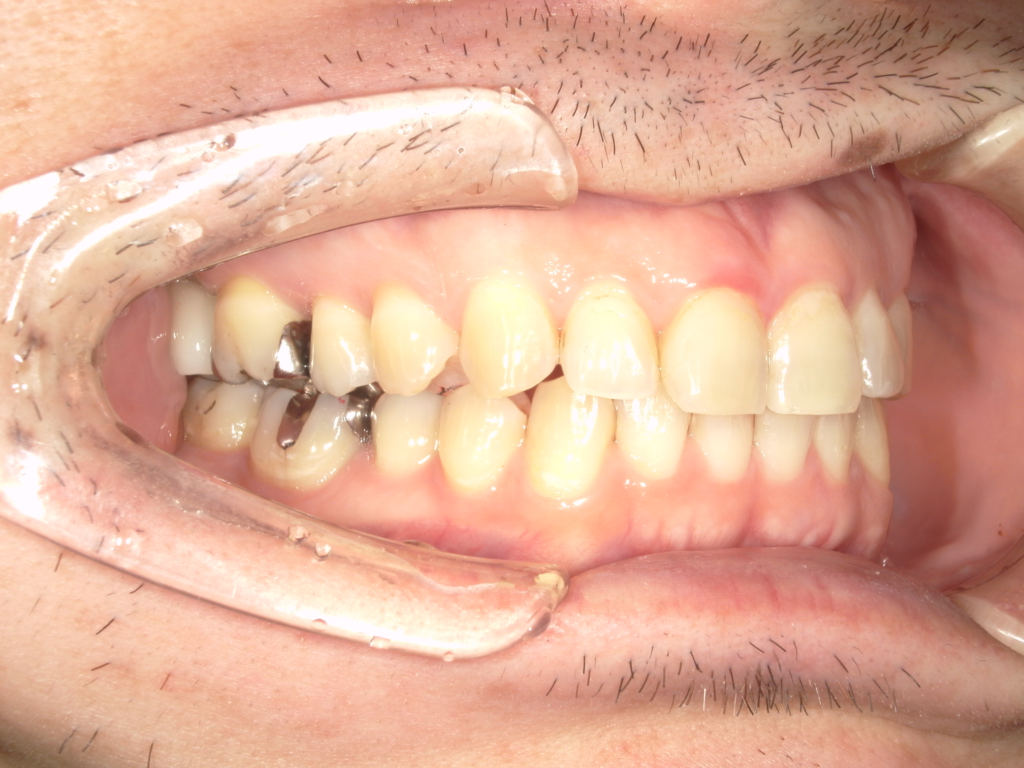

Y様インプラント実例 #44

左の上下の奥歯をインプラントで治療しています。

左下の奥歯は歯を抜くのと同時にインプラントの埋め込みを行っています。

被せものは上下、セラミックスで作っています。

治療前

治療後